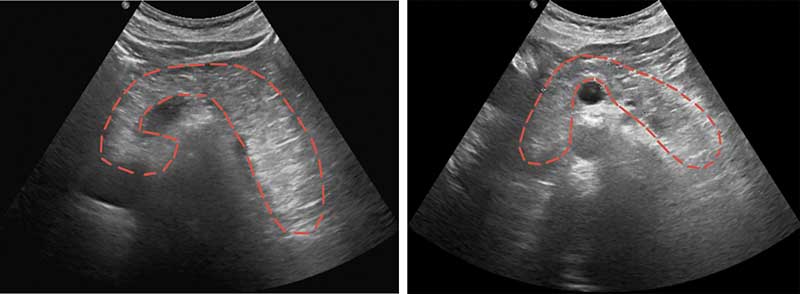

Рис. 1. УЗИ органов брюшной полости: поджелудочная железа не дифференцируется, эхогенность аналогичная эхогенности жировой клетчатки (липоматоз), ориентировочные контуры железы обведены красной пунктирной линией

Согласно данным ультразвукового исследования брюшной полости, контуры поджелудочной железы неровные, нечеткие, структура паренхимы диффузно неоднородная, эхогенность аналогичная эхогенности жировой клетчатки. Главный панкреатический проток не расширен (рис. 1).

Отличительной чертой ЛПГ ПЖ является ее бессимптомное течение и случайное выявление при инструментальном исследовании или при аутопсии. Клинические проявления развиваются, как правило, вследствие тяжелого нарушения экзокринной функции ПЖ. В представленном клиническом наблюдении основной жалобой пациентки было выраженное снижение массы тела. В ходе обследования пациентки были проведены стандартные лабораторные и инструментальные исследования. Сывороточные показатели панкреатических ферментов свидетельствовали о сниженной функции ПЖ. Уровень фекальной эластазы составил 3,1 мкг/г, что подтвердило предположение о тяжелой экзокринной недостаточности ПЖ. В анамнезе у пациентки не было острого или хронического панкреатита, а также других заболеваний ПЖ, которые могли бы привести к нарушению ее функции. Кроме того, не было выявлено никаких нарушений углеводного обмена. По данным УЗИ, ПЖ не дифференцировалась, ее эхогенность была аналогична эхогенности жировой клетчатки, что и характеризует термин «исчезающая» поджелудочная железа. Данные КТ наиболее достоверно позволили определить наличие тотального липоматоза ПЖ. По данным МРТ, ПЖ на фоне окружающей жировой клетчатки отчетливо не дифференцируется. При этом, по данным всех методов визуализиции, не было отмечено наличия каких-либо включений в паренхиму ПЖ, в том числе кальцинатов, а также отсутствовали изменения со стороны протоков. Все полученные данные позволили установить диагноз «ЛПГ с внешнесекреторной недостаточностью поджелудочной железы тяжелой степени» без применения инвазивного гистологического исследования.